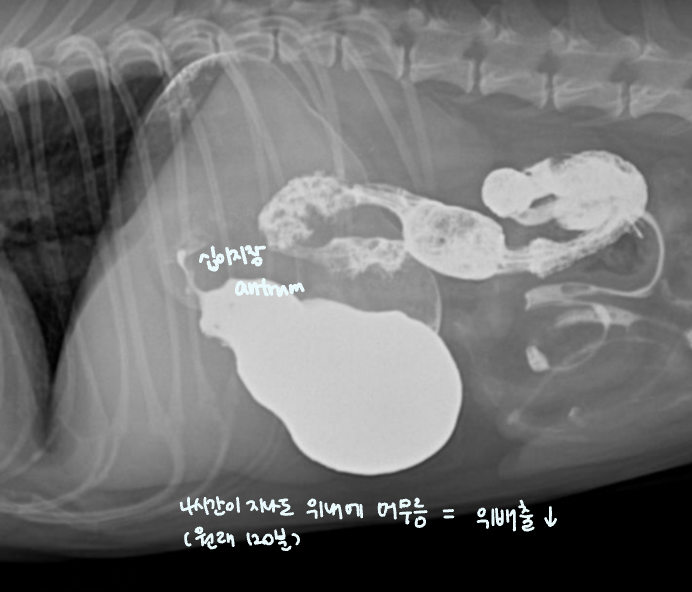

-

์กฐ์์ ๋ ๊ฐ์์ 1์๊ฐ 20๋ถ~2์๊ฐ, ๊ณ ์์ด์์ 1์๊ฐ ๋ด๋ก ๋ค ๋ฐฐ์ถ๋จ.

- ์ด๋ณด๋ค ์ค๋ ๊ฑธ๋ฆฌ๋ฉด ์์ ๋ฐฐ์ถ์ ๋ฌธ์ ๊ฐ ์๋ ๊ฒ. (๋ฐฐ์ถํ๋ ํ์ด ์ฝํด์ง, ํต๋ก๊ฐ ๋งํ, ์กฐ์์ ํก์ฐฉ/ํก์ ์ด๋ฌผ ์กด์ฌ)

| hairball, ์ฒ, ์ค (๊ณ ์์ด) - ์กฐ์์ ๋ฐฐ์ถ์ด ๋งค์ฐ ๋๋ฆผ (1์๊ฐ์ด๋ฉด ๋๊ฐ์ผ ํ๋๋ฐ, ๋ง 8์๊ฐ..) โ์ ๋จน๊ณ ์ ๋ ธ๋๋ฐ ๊ฐํ์ ์ผ๋ก ๊ตฌํ ํ๋ค โ โ ํค์ด๋ณผ ์์ฌ |

- pylorus๊ฐ ํ์๋๋ฉด, ์๋ฐฐ์ถ ๋ถ๋ฅ + ์์ฅ ๋ด gas๊ฐ ์ฐธ.

- ์๋ด ์กฐ์์ ๊ฐ ์ถ์ ๋จ. (gastric emptying ์ง์ฐ)